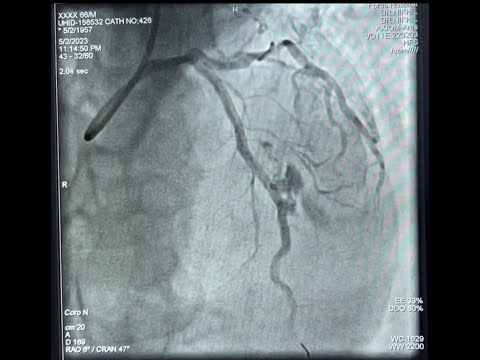

Case 70: PCI Manual - Ostial and distal RCA lesion